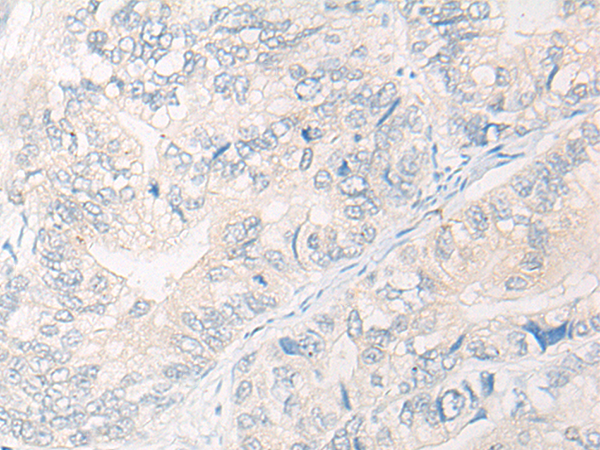

分类: 科研抗体货号: P13239别名:应用: IHC反应种属: Human